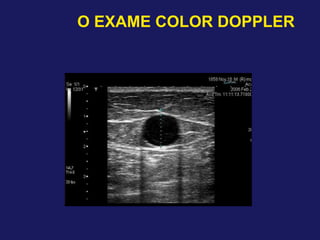

– Dimensões das veias safenas*

–Safena Interna na coxa

Até 4,0 mm: Habitual

4,1 a 5,0 mm: Limítrofe

>5,0 mm: Ectasiada

* Apenas Referência